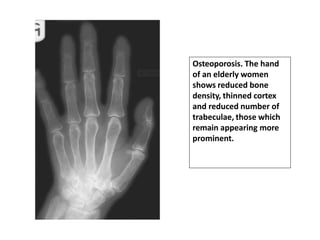

Hand:

•Thinning of cortex of the tubular bones.

•Accentuation of primary trabeculae with loss of secondary

trabeculae.

Osteoporosis. The hand

of an elderly women

shows reduced bone

density, thinned cortex

and reduced number of

trabeculae, those which

remain appearing more

prominent.